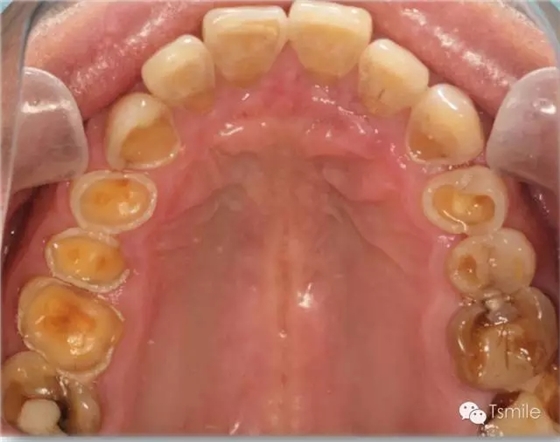

② 胃食管返流?。℅astroesophageal Reflux Disease,GERD)

胃食管返流病,英文名Gastroesophageal Reflux Disease,簡(jiǎn)稱GERD,是由于消化系統(tǒng)疾病導(dǎo)致胃液返流至口腔內(nèi),胃液接觸牙齒表面,胃酸對(duì)牙齒硬組織造成嚴(yán)重酸蝕脫礦。胃食管返流病導(dǎo)致的牙列重度磨耗主要發(fā)生于上頜牙齒的舌面以及下頜磨牙的頜面。胃食管返流病患者在夜間睡眠時(shí)胃液返流導(dǎo)致的牙齒酸蝕脫礦最為嚴(yán)重,由于患者的睡姿體位不同,因而造成牙齒酸蝕脫礦的部位和程度在牙弓左右兩側(cè)并不對(duì)稱。

圖5: 胃食管返流病導(dǎo)致的牙列重度磨耗